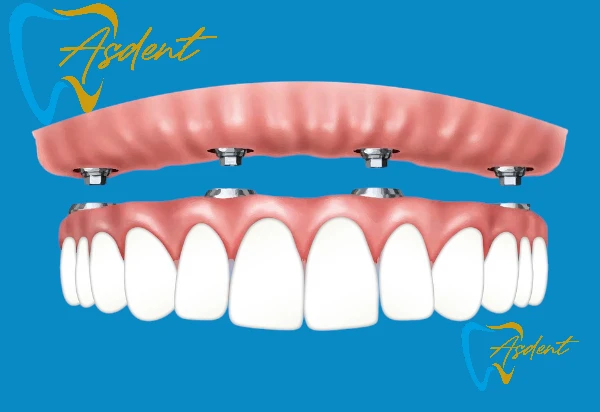

Пакет имплантатов All-on-4 / Имплантация в Турции

- Система фиксированных протезов на 4 имплантатах.

- Улыбка в тот же день с помощью временного протеза.

- Окончательный протез из фарфора или циркония.

- Необходимая рентгенография и осмотр.

- Все лекарства, контрольные осмотры и хирургический уход включены.

Преимущества: полный фиксированный протез челюсти с меньшим количеством имплантатов, быстрый результат, экономическая выгода.

Пакет имплантатов All-on-6 / Имплантация в Турции

- 6 имплантатами с полными зубами на челюсти

- Более прочные и долговечные результаты

- Необходимые рентген, томография и консультация

- Регулярные контрольные приемы после лечения

Преимущества: Дополнительная прочность и долгосрочный комфорт благодаря большему количеству имплантатов.

Пакет имплантатов All-on-8 / Имплантация в Турции

- Полный зубной ряд, поддерживаемый 8 имплантатами, фиксированный протез.

- Максимальная прочность и долговечные результаты.

- Включает панорамную рентгенографию, 3D CBCT-сканирование и подробную консультацию.

- Регулярные контрольные приемы после лечения.

Преимущества: Равномерное распределение силы на челюстной кости благодаря 8 имплантатам, дополнительная прочность, комфорт и долгосрочный успех, эстетический и функциональный результат, максимально приближенный к естественным зубам.